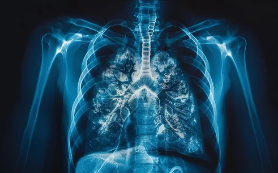

2. 호흡 곤란: 숨 쉴 때마다 답답함

늑골 골절은 폐 기능 저하로 이어져 호흡 곤란을 유발할 수 있습니다. 특히 다발성 늑골 골절이나 흉곽 골절의 경우 흉벽의 안정성이 떨어져 호흡 운동이 제한되고, 폐렴, 무기폐 등 합병증 발생 위험이 높아집니다.

호흡 곤란은 일상생활에 큰 지장을 주고, 심한 경우 생명을 위협할 수도 있습니다. 늑골 골절 후 호흡 곤란 증상이 나타난다면 즉시 병원을 찾아 응급 처치를 받아야 합니다.